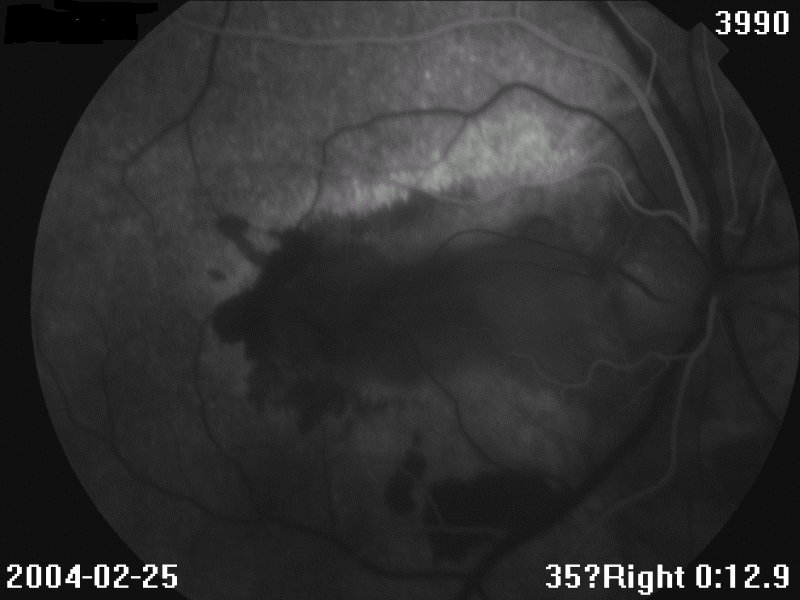

眼底见:玻璃体尘状混浊 眼底图 右眼 左眼 荧光造影图 眼科B超 OCT 视野 讨论: 1、诊断及鉴别诊断

4、FFA:早期低荧光,晚期高荧光;有荧光渗漏(CNV)、遮挡荧光(出血)

FFA:早期低荧光,晚期高荧光;如有CNV,可见荧光渗漏,或出血遮挡荧光。晚期病例:病灶边缘高荧光,中央低荧光,经常见大的脉络膜血管

ICGA:活动病灶为低荧光,脉络膜血管梗塞或渗出、水肿遮挡荧光